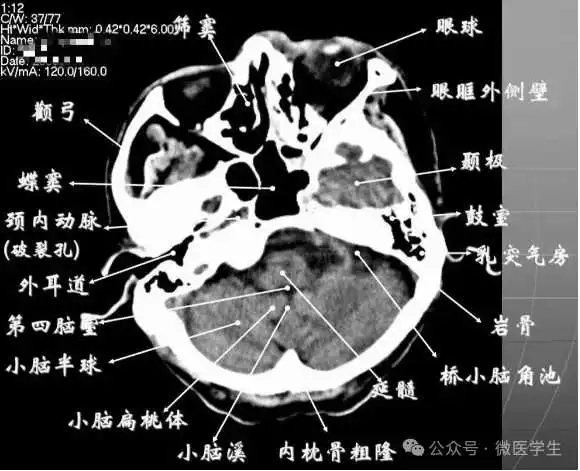

正常解剖

- 颅前窝底部:眼眶,眼球,筛窦,蝶窦,前床突等。

- 颅中窝:前界---蝶骨;后界---颞骨岩部(岩骨);内缘---海绵窦及垂体窝;外缘---颞骨,窝内为颞叶,其内侧为海马回。

- 颅后窝:前缘---岩骨;后缘---枕骨;鞍背后方---脑桥前池,向两侧延伸为脑桥小脑角池。

- 第四脑室:位于颅后窝中线上,后面紧邻小脑蚓部,其两侧为小脑扁桃体。

- 延髓、脑桥:位于第四脑室前。

- 颅前窝:颞叶。